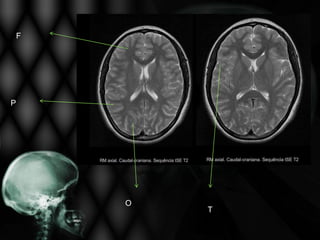

LOBOS TELENCEFÁLICOS

F

P

O

T

AVE ISQUÊMICO NA RM